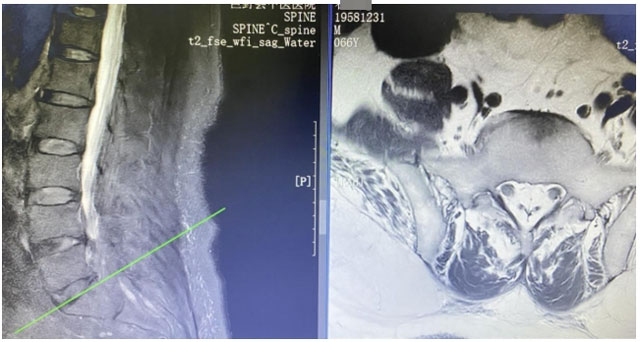

患者是一位66岁的男性,多年来深受下肢瘫痪和大小便失禁的病痛折磨。他曾辗转多家医院,尝试了针灸、理疗、药物等多种治疗方法,但症状不仅没有缓解,反而逐渐加重,最终导致下肢瘫痪和大小便失禁。绝望之际,患者经亲戚介绍来到巨野县中医医院骨伤一科就诊。 术前MR检查 骨伤一科学科带头人杨建安主任医师凭借丰富的临床经验,揭开了病痛的神秘面纱——一种罕见的“特发性椎管内硬膜外脂肪增多症”,这种病症是由于椎管内脂肪组织病理性增生,压迫马尾及神经根所致,常被误诊或漏诊。好发于男性,胸段及腰骶段。硬膜外脂肪增多症常见的病因多与长期摄入外源性甾体类激素、激素异常疾病、肥胖症等有关。 杨建安主任医师介绍,正常人的椎管内含有少量脂肪组织,但该患者的腰骶椎管内脂肪组织异常增多,对神经产生明显压迫,导致下肢瘫痪和大小便失禁。明确病因、完善术前检查并与患者及家属充分沟通后,决定为患者实施常规手术治疗,助他摆脱病痛折磨。手术过程顺利,术后患者恢复良好。 为了帮助患者尽快康复,骨伤一科护士长于凌带领护理团队为患者制定了详细的康复计划,每日督促并鼓励患者进行康复训练。在医护人员的悉心照料和患者及家属积极配合下,患者恢复良好,家属对治疗结果十分满意。 术后DR复查 巨野县中医医院骨伤一科始终致力于攻克疑难病症,以精湛的医疗技术和专业的护理服务为患者带来健康与希望,也展现了医院骨伤科在疑难病症诊疗方面的绝对实力。